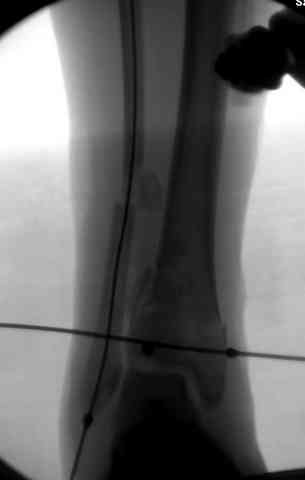

Снова приветствую вас, коллеги. К моменту вступления в обсуждение аксакалов, операция была, увы, выполнена(31.10.07.) Начали с доступа к наружной лодыжке, произвели ее фиксацию спицами, развернули кусок заднего края, наложили дистрактор, затем произвели дистракцию, фиксацию спицами дистального эпиметафиза б/бк,Рентгено-контроль. синтез наружной лодыжки 1/3пластиной. из двух коротких разрезов сформирован канал под медиальную тибиальную пластину LCP. Края ран ушиты без натяжения. Прочувствовать жесткость фиксации винтами с угловой стабильностью не удалось, поэтому дистрактор оставлен на энное время.

На представленных R-снимках не окончательный вид после остеосинтеза. Дистальная опора давила на стопу, пришлось ее сместить проксимально, в рез-те чего, она закрыла щель сустава, последние снимки не информативны.

И вправду. В аппарате - практически идеальная для данного случая репозиция (браво!). Пластинка только помешала( в плане возможных осложений), так как не добавит стабильности после снятия наружного фиксатора, (что не скоро будет). Спицы в аппарате, пожалуй, только добавят проблем с дальнейшим лечением (проксимально - я - за стержни). Вполне приемлимо бы было, добившись репозиции в дистракторе, провести спицы с упорными под ЭОП, срепонировать отломки и оставить как есть. А вероятный артродез произвесть в аппарате потом.